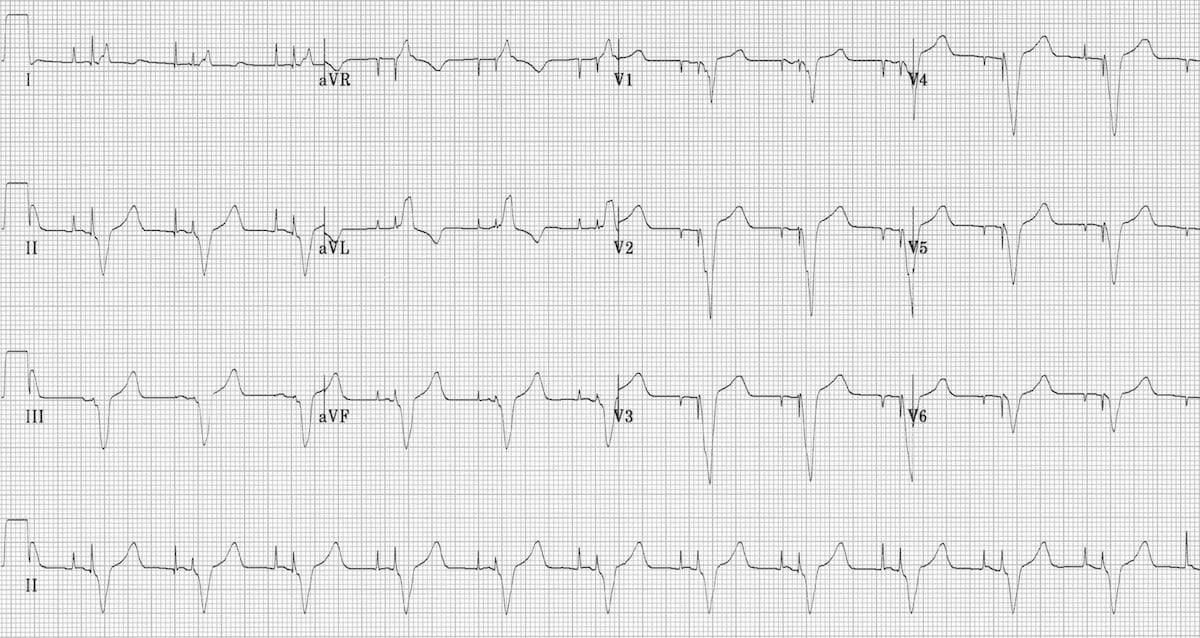

This is an ECG of monomorphic VT. Note the very regular, broad complex tachycardia and the same QRS morphology throughout.

https://litfl.com/ventricular-tachycardia-ecg-library/

© Life in the Fast Lane. Licensed under CC BY-NC 4.0